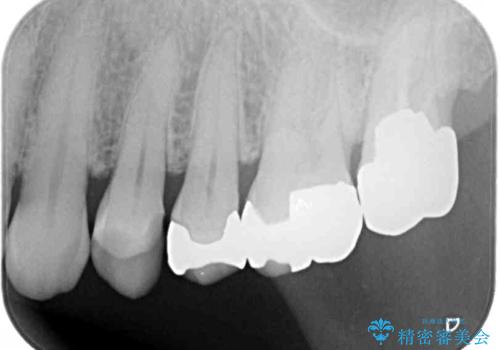

外れてしまった銀歯 セラミックインレーで自然な仕上がりに

- 奥歯の銀歯が外れてしまったため、セラミック治療を希望された患者様です。

セラミックインレーによる修復治療を実施しました。

正面から見える場所であったため、セラミックインレーで自然な口元にすることができました。